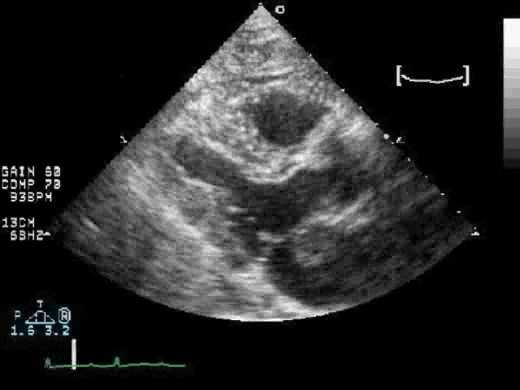

Трансторакальная и чреспищеводная эхокардиография для выявления причины эмболии

Чувствительность трансторакальной эхокардиографии (TTЭхоКГ) для обнаружения потенциальных источников эмбола низкая, так как наиболее частые потенциальные причины плохо визуализируются с помощью этой методики. При отсутствии клинических сердечных заболеваний диагностическая ценность составляет всего 1%, а с клиническими сердечными аномалиями увеличивается до 15%. Его основное применение - оценка глобальной и региональной систолической функции ЛЖ и апикального тромба в левом желудочке.

Оценка межпредсердной перегородки и грудной аорты. В целом чреспищеводная эхокардиография (ЧПЭХоКГ) выявляет значительно больше потенциальных источников эмболии, чем TТЭхоКГ (39-57% против 15-19%). Оценка потенциального источника эмбола в настоящее время является основным клиническим показанием для ЧПЭХоКГ в большинстве лечебных учреждений (26%). Использование контраста могло бы повысить эффективность ЧПЭхоКГ для обнаружения тромбов в ушке левого предсердия, и польза была максимальной, когда исследования были ограничены наличием спонтанного эхо-контрастирования или когда была низкая скорость опорожнения ушка левого предсердия. Кроме того, контраст часто помогает отличить плотный спонтанный эхоконтрастный осадок и необходим для оптимальной визуализации ЛП и тромба, в частности, расположенной сзади ушка левого предсердия (наиболее частое место расположения тромба). Однако, вероятно, лучше рассматривать эти два метода как взаимодополняющие, а не исключающие друг друга.